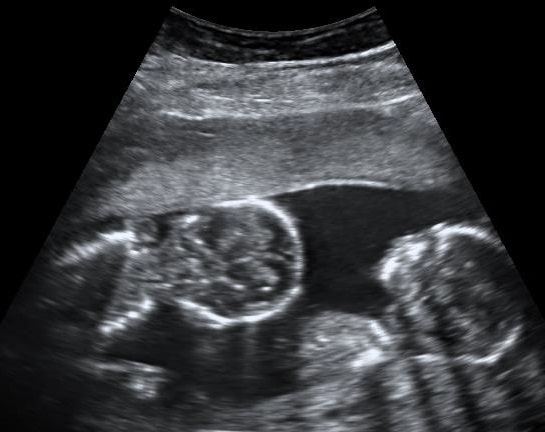

In addition to these problems, IVF usually involves the fertilization of multiple embryos. This means that a woman may be pregnant with multiple children. They then selectively abort “extra” embryos to make room for one or two. Medical professionals refer to this process as “pregnancy reduction.”

Twins at 15 weeks. By Mikael Häggström, used with permission